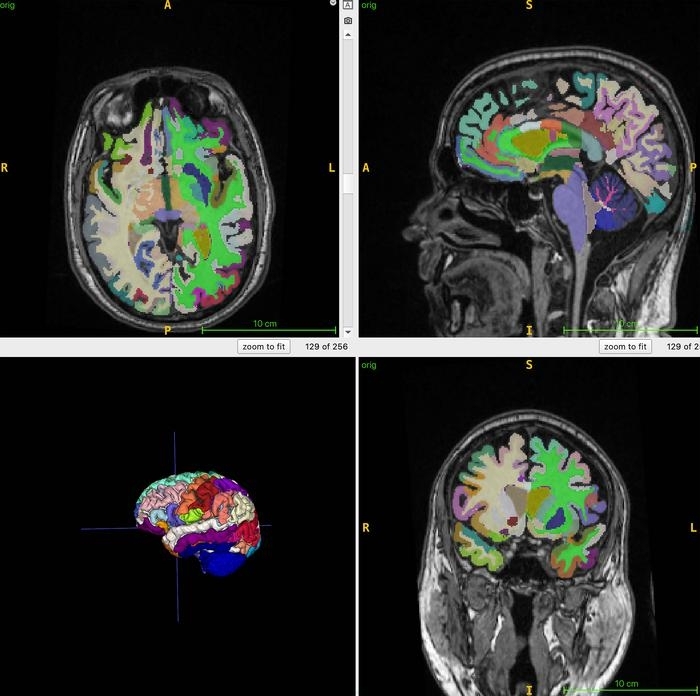

인공지능이 뇌 나이를 계산할 때 사용하는 3차원 T1 용적 MRI 스캔에서 얻은 데이터. 뇌를 여러 영역으로 나누어서 각 부분의 부피를 어떻게 측정했는지 보여준다.

연구팀은 건강한 성인 남녀 1164명을 대상으로 전신 MRI 검사를 했다. 연구팀은 지방은 밝게, 액체는 어둡게 보여줘 근육, 지방, 뇌 조직을 최적으로 영상화할 수 있게 하는 T1 강조 영상 기법을 결합했다.

연구팀은 MRI-T1 영상을 인공지능 알고리즘을 사용해 전체 근육량, 내장 지방, 피하 지방, 뇌 나이를 정량화했다.